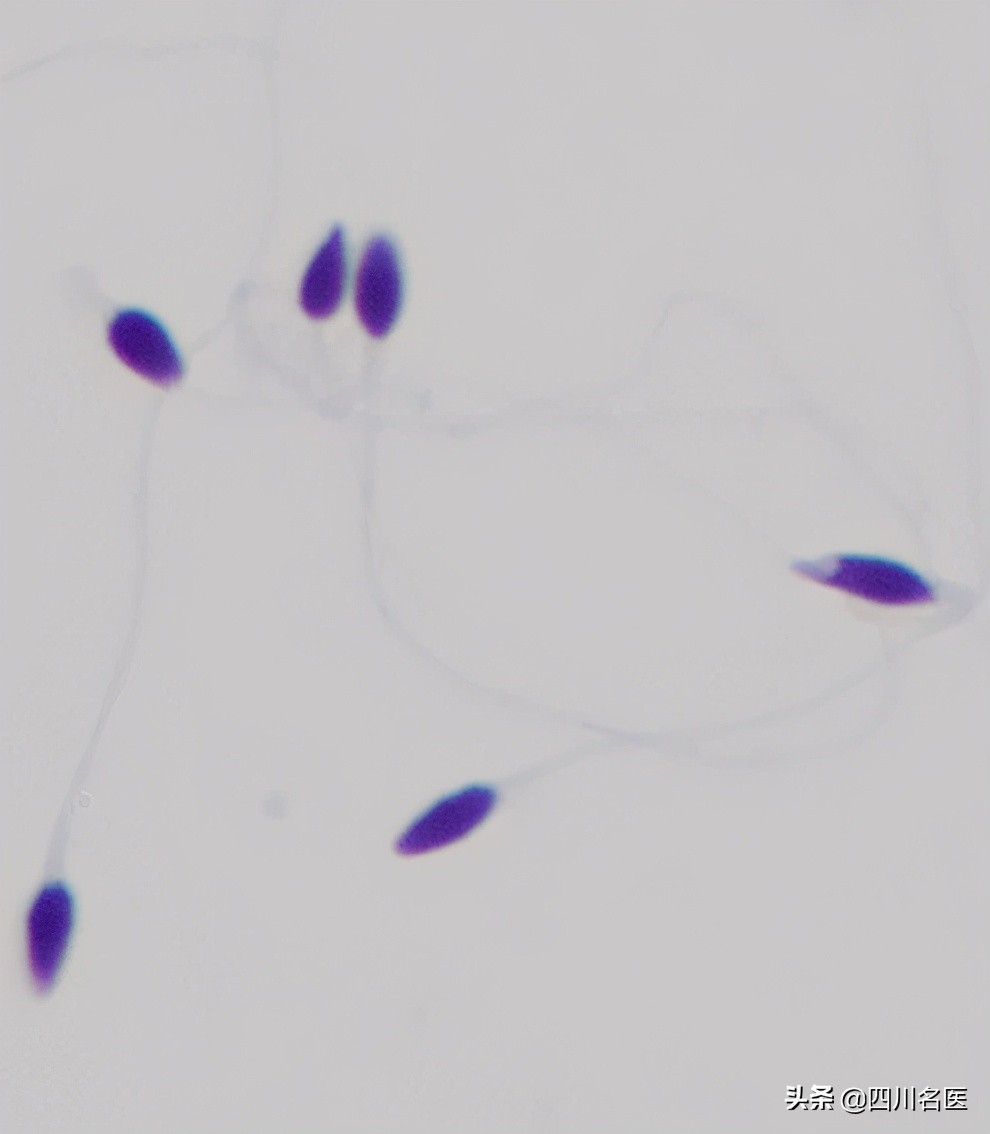

▲多头多尾精子

▲锥形头精子

▲精子头部顶体区空泡

▲梨形头精子

▲精子中的“大脖子病” and “歪脖子病”